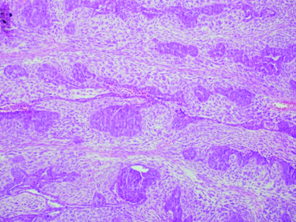

Histopathologic examination of the mass (Haematoxylin and Eosin Staining x 10). Cells forming rosette like structures and various types of sarcomatous components. OMMMT of the ovary has been classified depending on the characteristics of the stroma. These stromal components may be either homologous (composed of tissues native to the ovary) or heterologous (containing tissues not normally found in the ovary, most commonly malignant cartilage or skeletal muscle). The epithelial component is often classified as serous, endometrioid or undifferentiated adenocarcinoma but may also represent clear cell adenocarcinoma or squamous cell carcinoma.